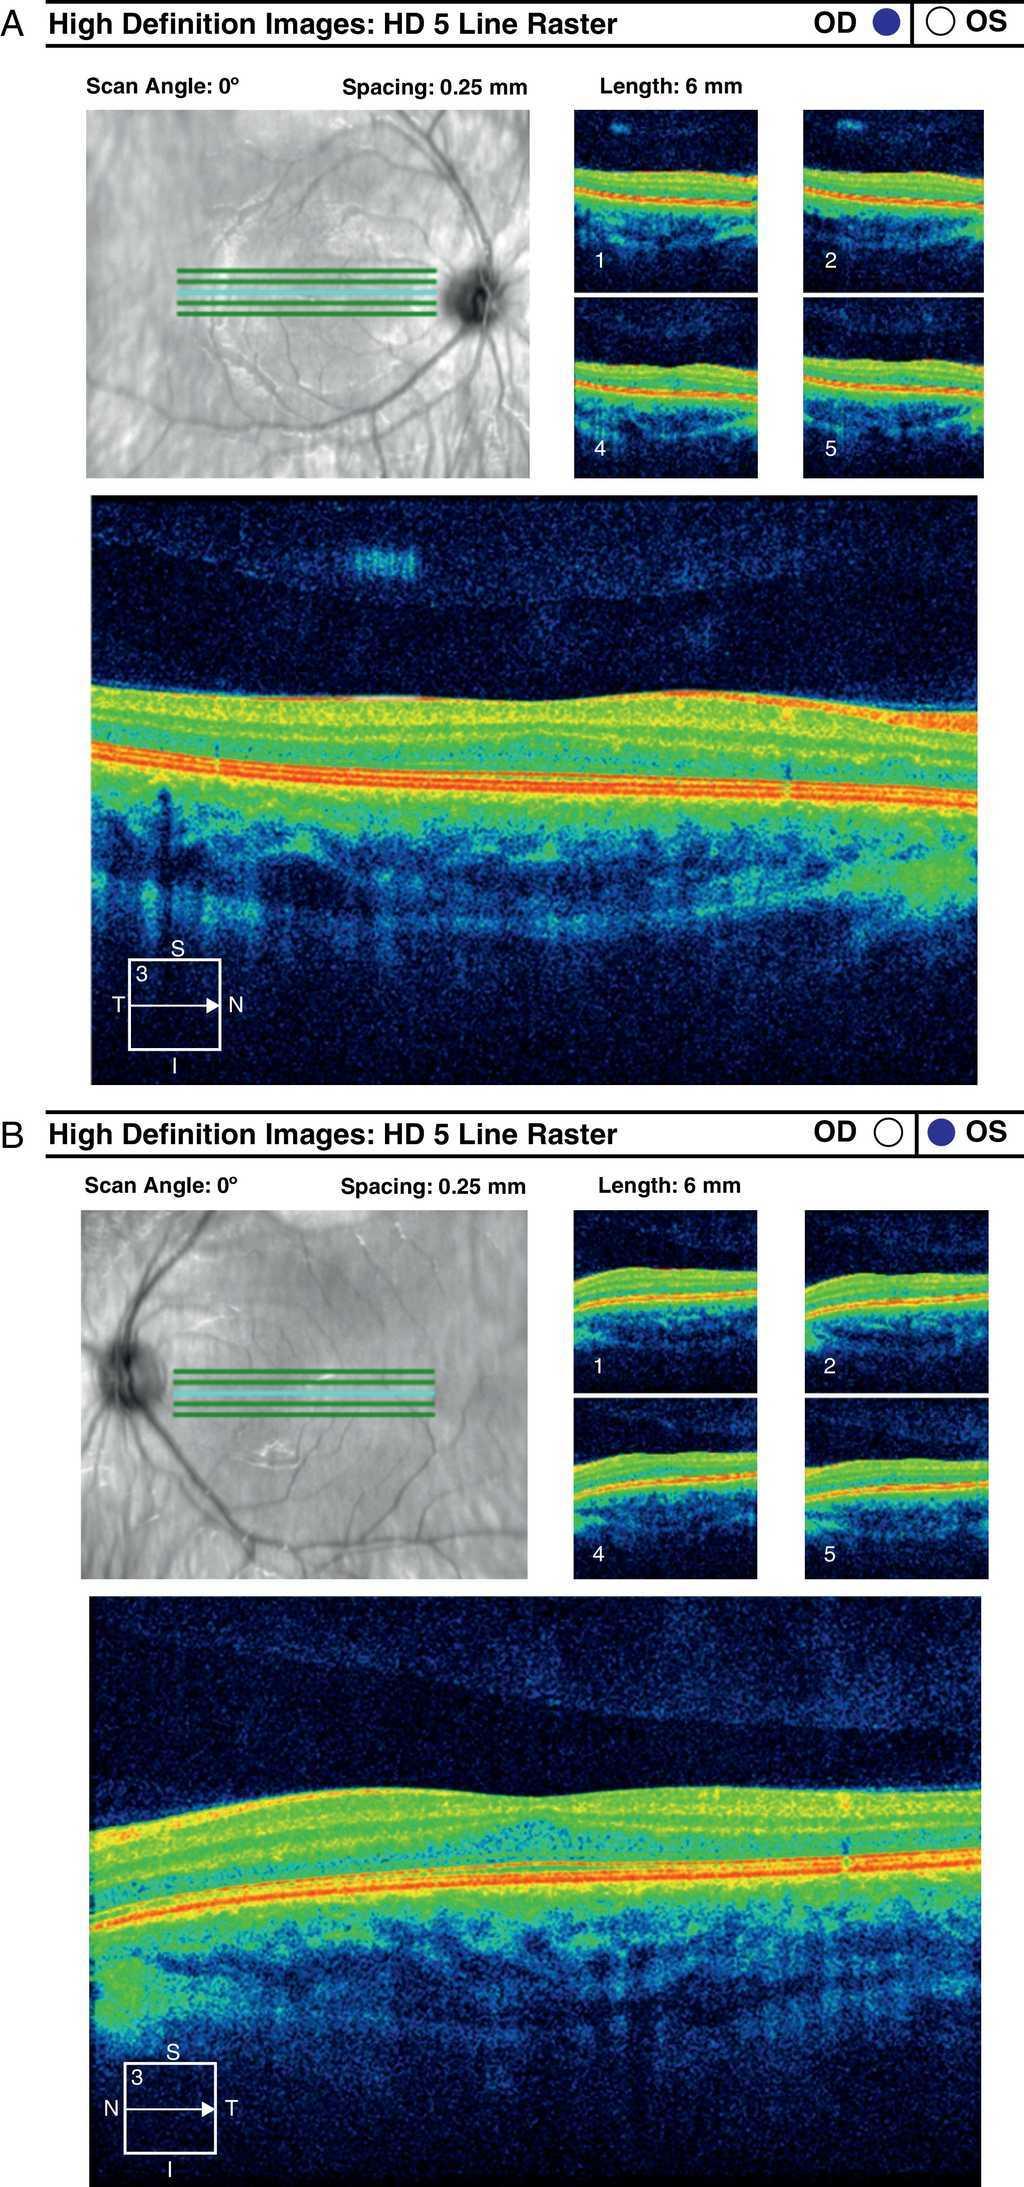

Measurement of macular pigment optical density. Download Scientific Macular Pigment Optical Density Measurement we investigated whether there was also a relationship between macular pigment optical density (mpod) and. currently, the most commonly used method in clinical practice for the measurement of the macular pigment. Measurement of mpod is achievable with a wide range of techniques, which are typically categorized into one of. macular pigment optical density (mpod) is an assessment. Macular Pigment Optical Density Measurement.

Figure 1 from Evaluation of Macular Pigment Optical Density in Healthy Macular Pigment Optical Density Measurement in the present article, we describe a simplified device for measuring mp optical density that can be applied to diverse. currently, the most commonly used method in clinical practice for the measurement of the macular pigment. accurate assessment of the amount of macular pigment (mpod) is necessary to investigate the role of. macular pigment optical density. Macular Pigment Optical Density Measurement.